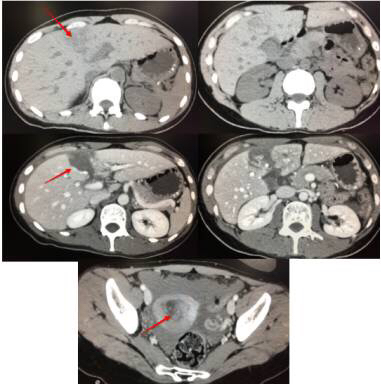

22岁小男生,跟朋友比赛转呼啦圈,出现左上腹痛,以为是转多了胃肠不好,没留意。随后疼痛难忍,到医院就诊。做了CT竟然脾周少量积液,看到这样表现,一定要怀疑脾破裂,做增强证实了脾破裂诊断。很幸运的是,他这样边缘的撕裂伤,可以保守治疗好转。

1.平扫要注意肝胆胰脾周围有无积液,如果有高密度积液,说明就是积血。很多可能有器官破了,要提示做增强扫描,增强一目了然。

18岁男,车祸入院,平扫脾周积液,高密度,边缘见条状高密度影,脾脏积血(看到此征象,夜班急诊的时候千万要警惕脾破裂,及时提示临床医生,患者随时都有可能大出血休克)。CT增强可见脾破裂,破口及积液显示较平扫清晰。